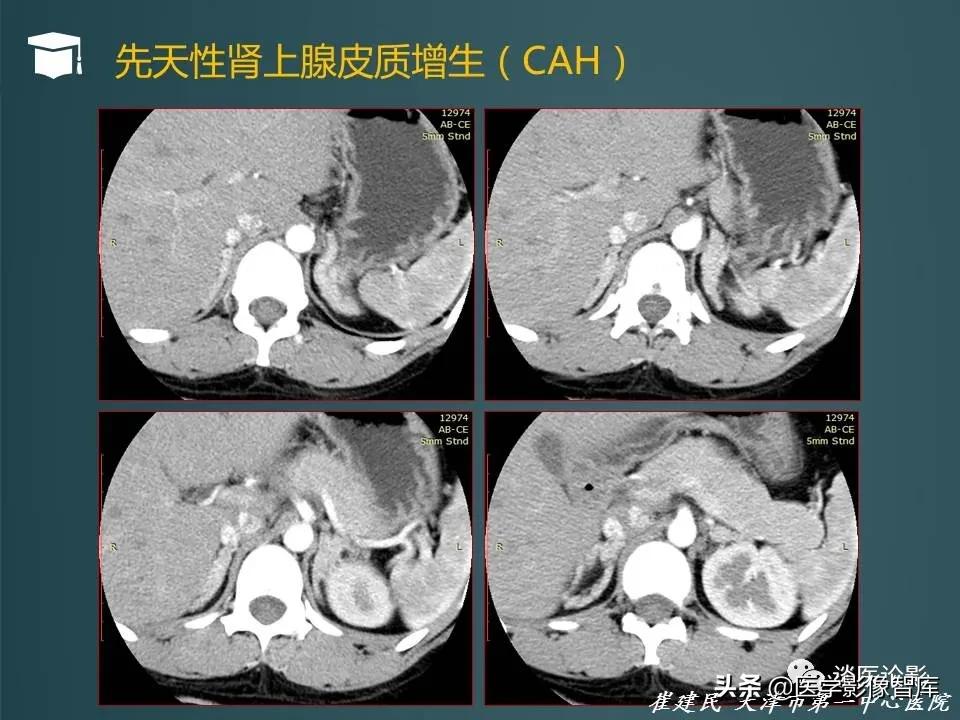

- 肾上腺皮质增生可以分为三种主要种类:ACTH依赖性、非ACTH依赖性、先天性肾上腺增生(CAH)